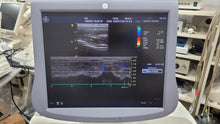

* Model Name : Used GE Vivid7 dimension & 2 Probe M12L M4S

* Condition : Used. (Working Excellent)

*GE Vivid7 Dimension Unit

*GE M12L Linear Probe

*GE M4S Cardiac Probe

*Aloka UST-9118 Vaginal Probe-1Pcs